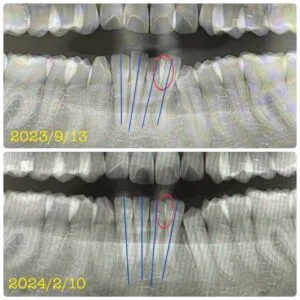

・写真2枚目、3枚目の赤⭕️部分は、重なり合っていた歯の重なりがなくなった箇所

・写真3枚目の青いたて線は、歯の傾き(歯軸)が改善された箇所

一箇所、記入漏れがありました…。

写真3枚目、下の歯の左から数えて4本目の歯です。

歯の向きが変わっています🦷

青線の前歯の軸が揃いつつある=前歯のガタ付きも改善されてきました。